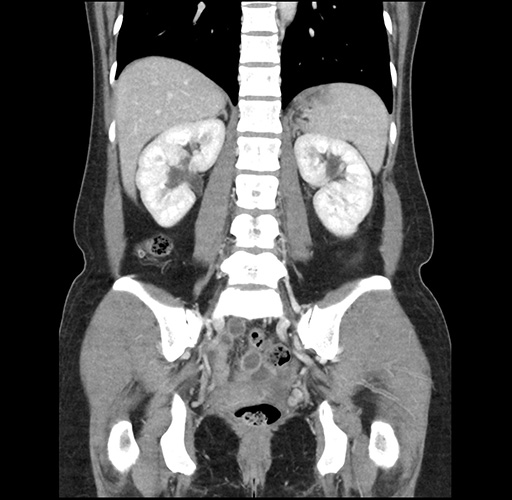

Imaging Analysis

Look through the patient's CT scan to identify any areas of concern for the necessary procedure.

Based on your CT findings, which issue(s) would give reason for "planned slowing down moment(s)" in this case?

Considering a standard left lateral sectionectomy procedure, what step(s) of the operation would you do differently in this case ?